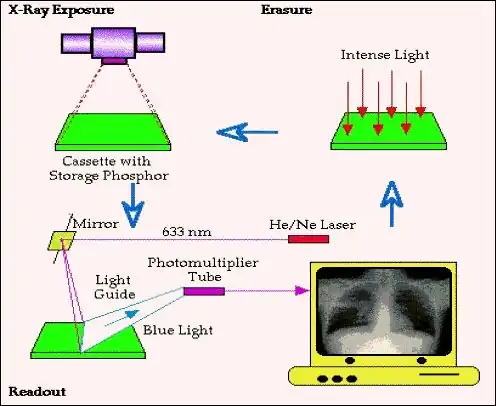

- This method of recording a projection radiograph is based on exploiting the photostimulable luminescent properties of barium fluorohalide compounds. The phosphor is layered on an imaging plate which when mounted in a cassette is used in place of the film/screen cassette used traditionally in radiography. The imaging plate is sometimes referred to as a storage phosphor because it stores a latent image following the radiation exposure which can be scanned afterwards using a readout device – as illustrated in the following figure:

- The figure shows the radiation exposure in the top left where the cassette is placed anterior to the patient to record the projected image. The cassette is then placed in a readout device (follow the blue downward arrow!), where it is scanned by a laser beam to digitize the latent image. The cassette can then be prepared for re-use by exposing it to intense incandescent light to erase any residual latent image information (top right in the figure above).